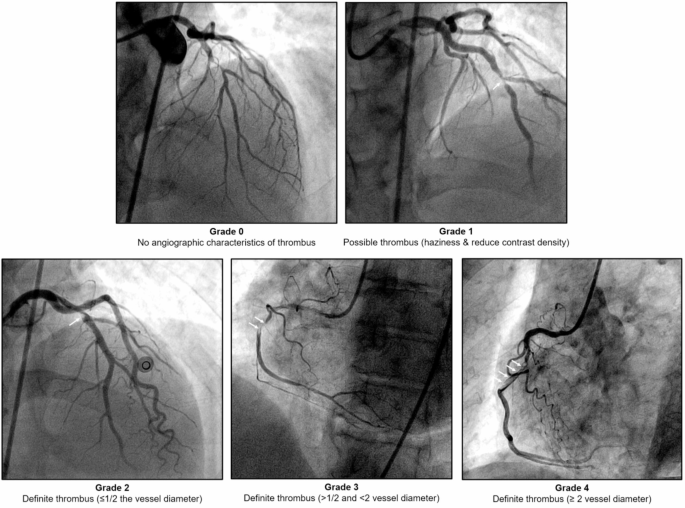

Intracoronary thrombus burden was angiographically assessed and classified into the following grades (Fig. 1); in grade 0, no angiographic characteristics of thrombus are present; in grade 1, a possible thrombus is present; in grade 2, there is a definite thrombus, with the greatest dimensions ≤ 1/2 the vessel diameter; in grade 3, there is a definite thrombus but with greatest linear dimension > 1/2 but < 2 vessel diameters; and in grade 4, there is definite thrombus, with the largest dimension ≥ 2 vessel diameters16. If the vessel is occluded, the thrombus burden was graded into one of the previous grades after flow achievement either with wire crossing or a small balloon (1.5 mm diameter) passage or dilatation. Intracoronary thrombus burden grade 4 was considered a high thrombus burden.

Patients’ angiographic and procedure characteristics are shown in Table 3. No significant difference between the unlikely/possible FH and the probable/definite FH groups was found for the location of the infarcted-related artery (p = 0.462). Compared to the unlikely/possible FH group, patients in the probable/definite FH group had a higher Syntax score (24.91 ± 5.8 vs. 18.66 ± 4.0, p < 0.001) and more frequent three-vessel disease (29.2% vs. 17.5%, p = 0.007) (Fig. 3A). Moreover, Fig. 4 shows that the DLCN score had a significant positive moderate correlation with the Syntax score (r = 0.592, p < 0.001) among the total studied patients. In addition, a significantly high thrombus burden and final TIMI slow/no-reflow were found among patients of the probable/definite FH group compared with the unlikely/possible FH group (p = 0.006 for the former and p = 0.027 for the latter) (Fig. 3B & C, respectively) with a trend toward the use of Glycoprotein IIb/IIIa inhibitors in patients of the probable/definite FH group (p = 0.07). Moreover, in multivariate analysis of the studied patients, males < 55 years, LDL-C level, probable/definite FH, and the number of diseased vessels were independent predictors of high thrombus burden (p-value 0.02, < 0.001, 0.004 and 0.019 respectively) (Table 4).